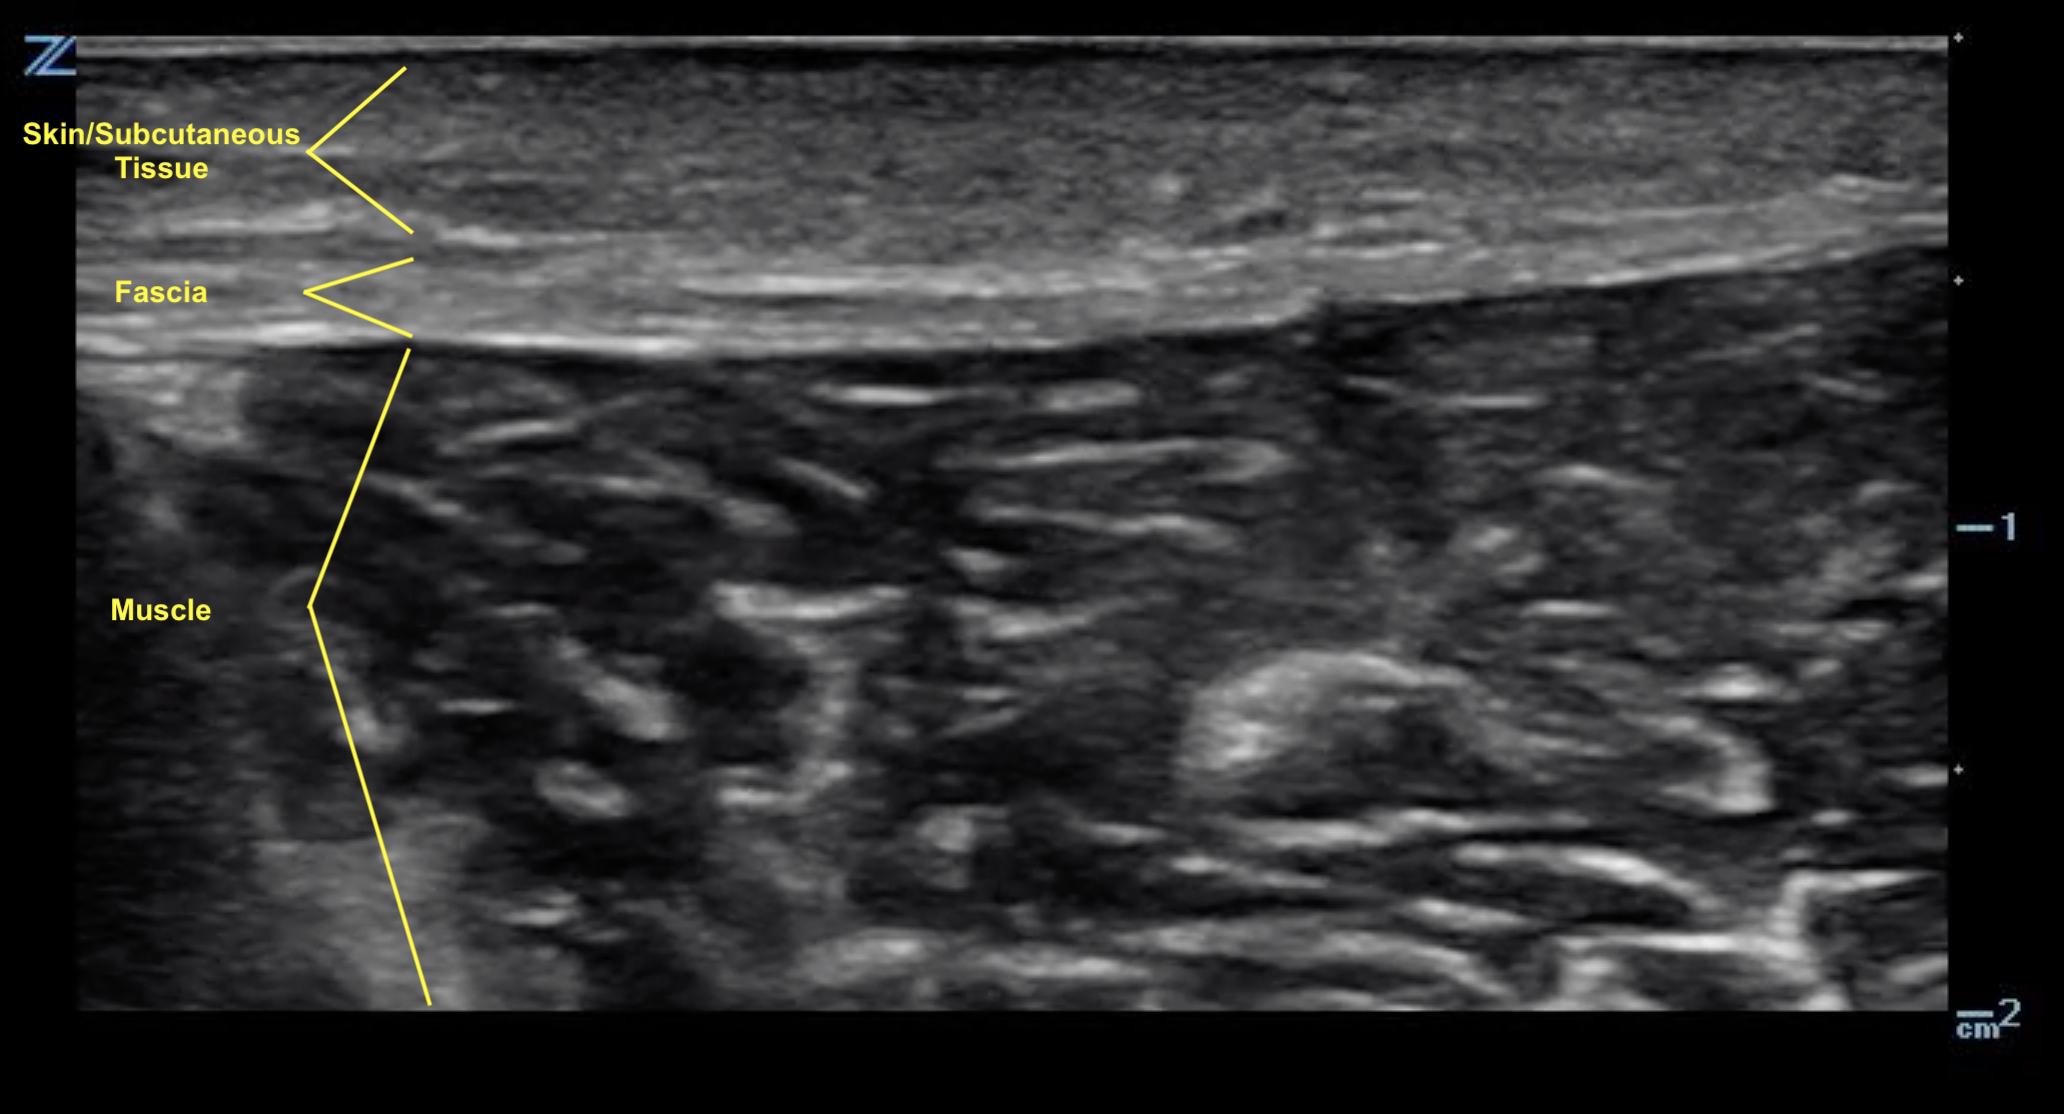

- Figure 1. Normal skin, subcutaneous tissue, and fascia.8

- With the equipment typically used for bedside ultrasonography, the epidermis and dermis cannot be differentiated. They appear together as a thin, hyperechoic layer.8

- The subcutaneous layer appears hypoechoic on ultrasound, with two components: hypoechoic fat interspersed with hyperechoic linear echoes running mostly parallel to the skin, which represent connective tissue septa.

- Veins and nerves can be visualized within the subcutaneous layer.

- Fascia appears as a linear hyperechoic layer. Its thickness will vary depending on the location.